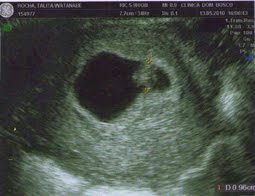

Nem acredito, consegui ver minha benção, ouvir o coraçãozinho dele, foi muita, muita, muitaaa emoção. Da clínica eu iria direto para a casa da minha sogra para depois viajar, mas eu tinha que vir aqui primeiro contar pra vocês e compartilhar com vocês. É uma emoção indescritível, conhecê-lo, ouvir o coraçãozinho batendo, eu e o papai ficamos todos bobos. O melhor pude ver o

Ultrassom todinho. Olhem as fotinhas:

Medida do embrião: 9mm

Idade Gestacional: 7 semanas e 2/7 dias